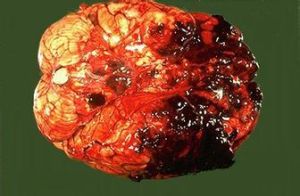

腦室內出血(一)早期腦內出血:也叫原發性腦內出血,指外傷後即刻或不久發生的出血,比較常見。因暴力的直接作用導致腦組織及血管同時損傷,或腦組織內血管單獨損傷所引起。其出血範圍常較大,單發或多發,有占位效應。如動脈出血,則出血範圍較靜脈出血時廣泛。有時在大片出血的周圍可見點狀出血,多是由於暴力作用引起局部血液循環紊亂而發生,常在傷後一段時間才出現。大片出血發生的部位多為暴力作用衝擊的部位,如暴力作用局部的大腦皮質下層的白質、基底節和腦幹。對沖性腦內出血可能程度更重,傷者多有明顯的顱內高壓症狀和體徵。如出血發生在腦幹,則傷後持續性深度昏迷。如果出血範圍較大或位於腦幹,死亡率常較高且發生較快。死因常為腦幹損傷出血、腦疝形成。這種出血即使經過手術治療,死亡率也較高。腦內出血經頭部CT掃描,在腦實質內發現局灶性高密度影即能診斷。較小的腦內血腫經過一周左右多可被液化、吸收,或機化形成瘢痕。較大的血腫如沒有很快死亡,一般在傷後2~3周內纖維包裹,血凝塊可液化,而成為囊腫。囊腫壁和瘢痕處因含吞噬含鐵血黃素的巨噬細胞而呈棕黃色,說明是因出血而非腦軟化的結果。小的點狀出血多數可完全吸收而不留痕跡。腦內血腫如較大,有時可破入鄰近的蛛網膜下腔或腦室。

外傷性腦內出血或血腫,法醫學屍檢一般容易發現,法醫學鑑定的關鍵是與病理性腦出血的鑑別。外傷性者可以年齡較輕,以大腦額葉、顳葉皮質下白質多見,可呈多發性,頭部外傷史明確,且頭皮損傷常較重,有時伴顱骨骨折,或伴腦挫裂傷、硬腦膜外或硬腦膜下血腫、蛛網膜下腔出血等;病理性腦內出血多見於中老年人,既往有或能檢出高血壓、高血脂、動脈硬化等病史,出血以基底節、枕葉、橋腦和小腦髓質多見,常為孤立性血腫。頭部外傷史缺乏或不明確、無頭部外傷、或外傷程度很輕與腦內血腫大小不相稱。偶爾單純屍檢很難將外傷性與病理性腦出血區分開來。還可能外傷與原有疾病在血腫發生上都起了作用,此時涉及外傷與疾病的關係。